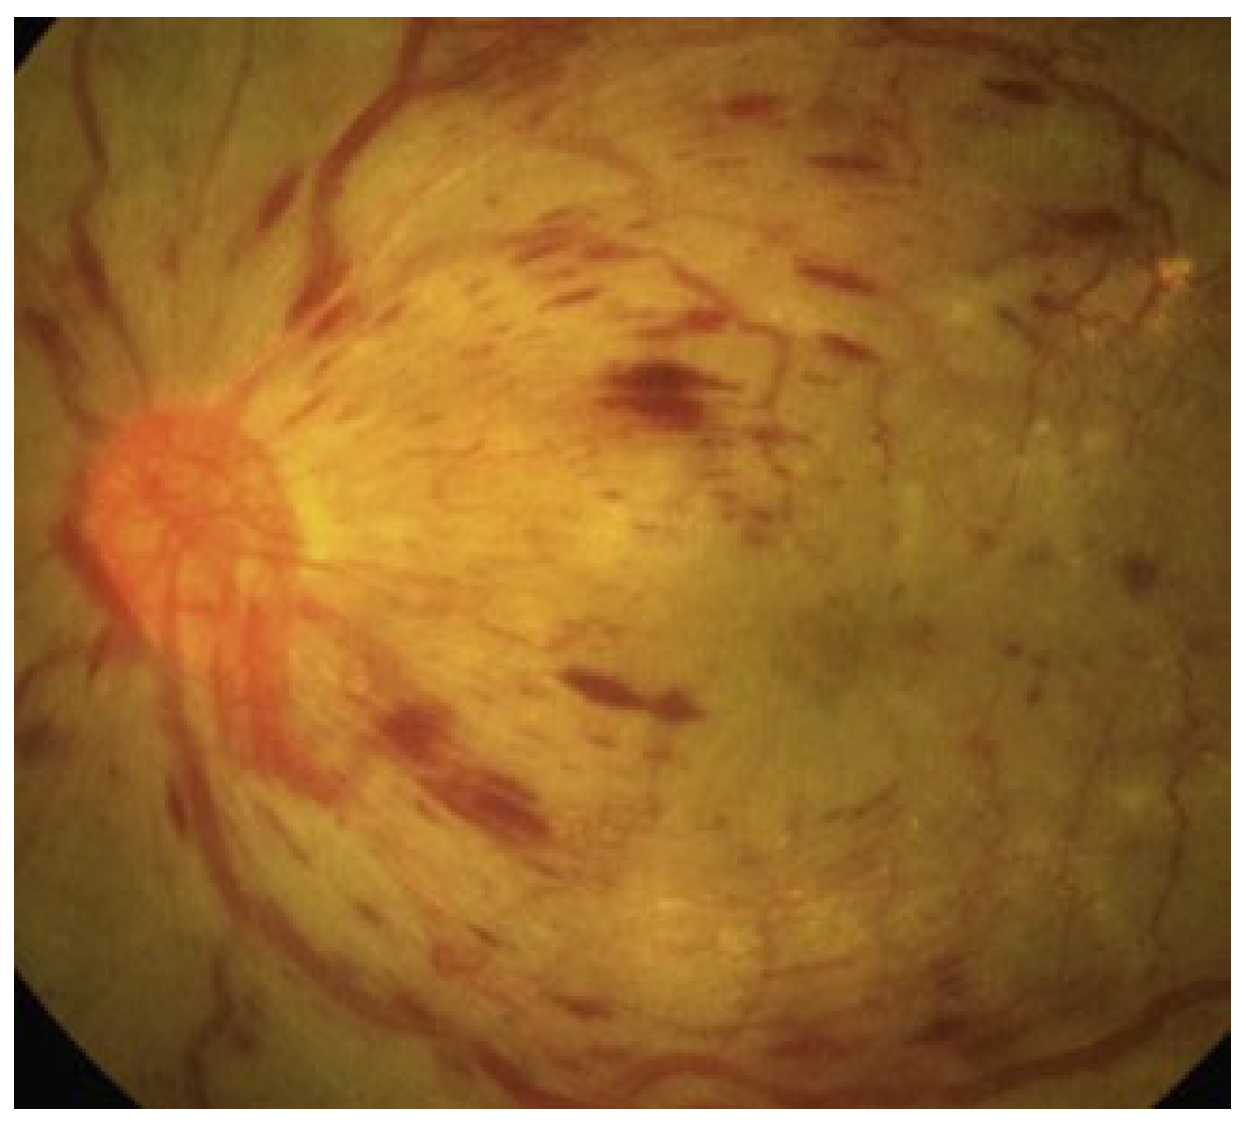

2.1. Non-Proliferative Diabetic Retinopathy (NPDR) and Proliferative Diabetic Retinopathy (PDR)